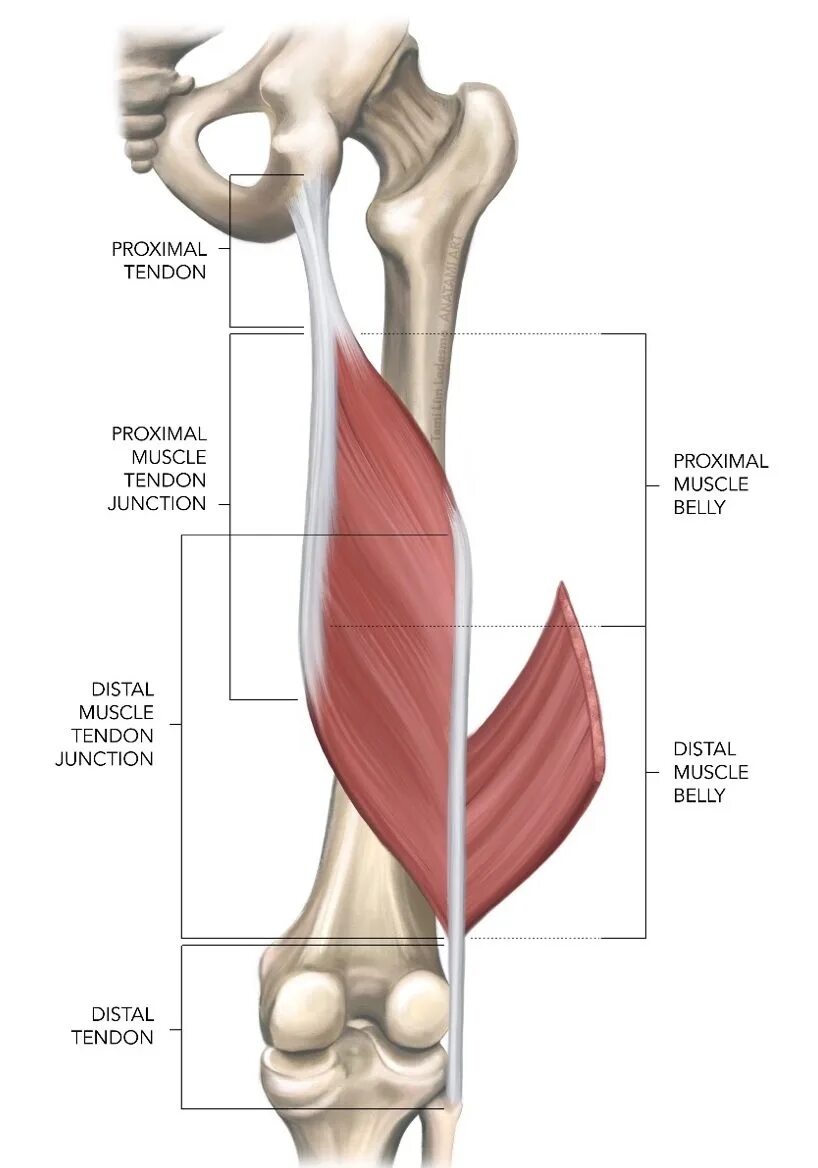

Хамстринг синдром тазобедренного сустава